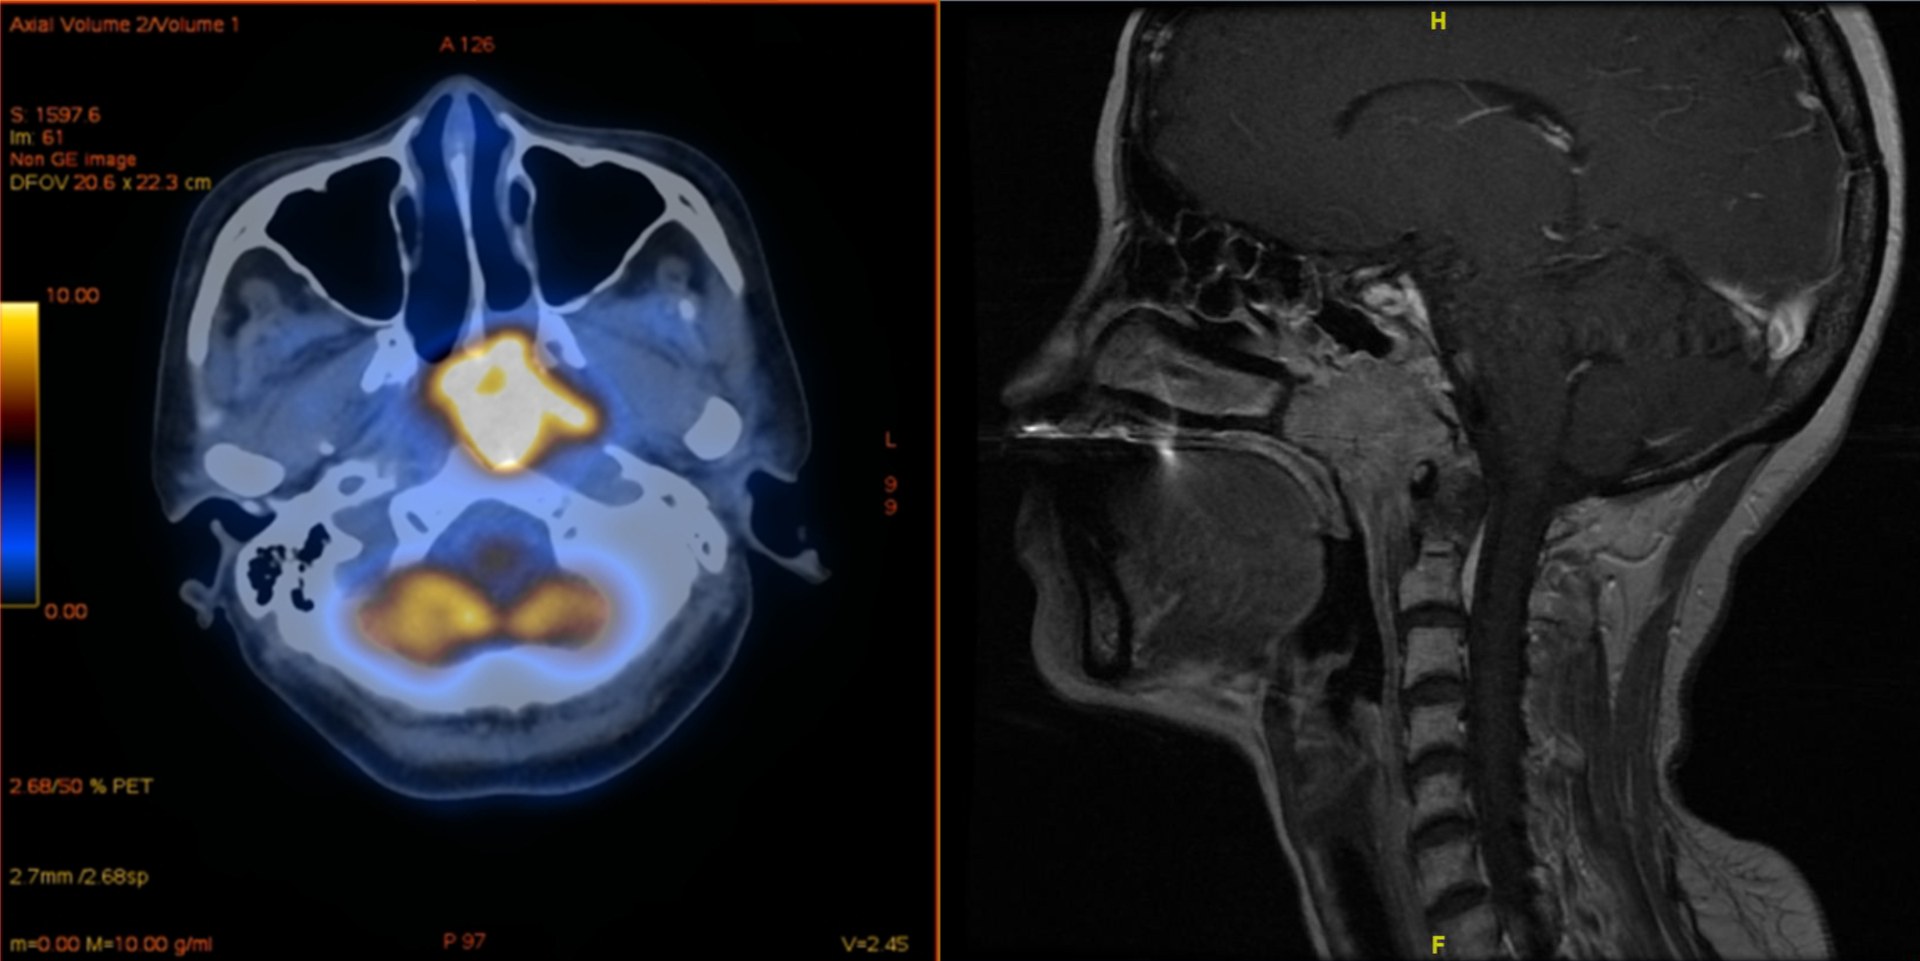

കോവിഡ് വാക്സിൻ അർബുദ ചികിത്സക്ക് ഗുണകരമായെന്ന് പഠനം. ജർമനിയിലെ ബോൺ, ചൈനയിലെ ഷാൻഷി സർവകലാശാലകൾ നടത്തിയ പഠനമാണ് ഇക്കാര്യം വ്യക്തമാക്കിയത്. നാസോഫറിംഗൽ അർബുദ മരുന്നുകൾ കോവിഡ് വാക്സിൻ ഉപയോഗിച്ചവരിൽ കൂടുതൽ ഫലപ്രദമായെന്നാണ് ഗവേഷകർ അറിയിച്ചത്. തൊണ്ടയ്ക്ക് ബാധിക്കുന്നതാണ് നാസോഫറിംഗൽ അർബുദം. ഇതിനെതിരെയുള്ള ചികിത്സ വാക്സിൻ സ്വീകരിക്കാത്ത രോഗികളേക്കാൾ വാക്സിനെടുത്തവർക്കാണ് ഫലപ്രദമാകുന്നതെന്നാണ് കണ്ടെത്തിയിരിക്കുന്നത്.

23 ആശുപത്രികളിൽ നാസോഫറിംഗൽ അർബുദ രോഗത്തിന് ചികിത്സക്കപ്പെട്ട 1537 പേരെ നിരീക്ഷിച്ചാണ് പഠനം നടന്നതെന്ന് സയൻസ് അലേർട്ട് റിപ്പോർട്ട് ചെയ്തു. 373 പേർ അർബുദ രോഗ ചികിത്സക്ക് മുമ്പേ ചൈനയിൽ നിന്ന് നിർമിച്ച സിനോവോക് കോവിഡ് വാക്സിൻ സ്വീകരിച്ചിരുന്നു. വാക്സിൻ സ്വീകരിച്ചവർ നന്നായി ആൻറി പിഡി വൺ തെറാപ്പിയോട് പ്രതികരിച്ചതായി ബോൺ യൂനിവേഴ്സിറ്റിയിലെ ഇമ്യൂണോളജിസ്റ്റ് ക്രിസ്റ്റിയൻ കുർട്സ് പറഞ്ഞു. അവർക്ക് ഗുരുതര അനന്തര ഫലങ്ങൾ നേരിടേണ്ടി വന്നില്ലെന്നും വ്യക്തമാക്കി. കഴിഞ്ഞ മൂന്നു വർഷമായി ലോകത്തിലെങ്ങും കോവിഡ് വാക്സിൻ ചർച്ച വിഷയമാണ്. മില്യൺ കണക്കിന് ജനങ്ങളെ വാക്സിൻ കോവിഡ് മഹാമാരി മൂലമുള്ള മരണത്തിൽ നിന്ന് രക്ഷിച്ചതായാണ് നിരീക്ഷിക്കപ്പെടുന്നത്.